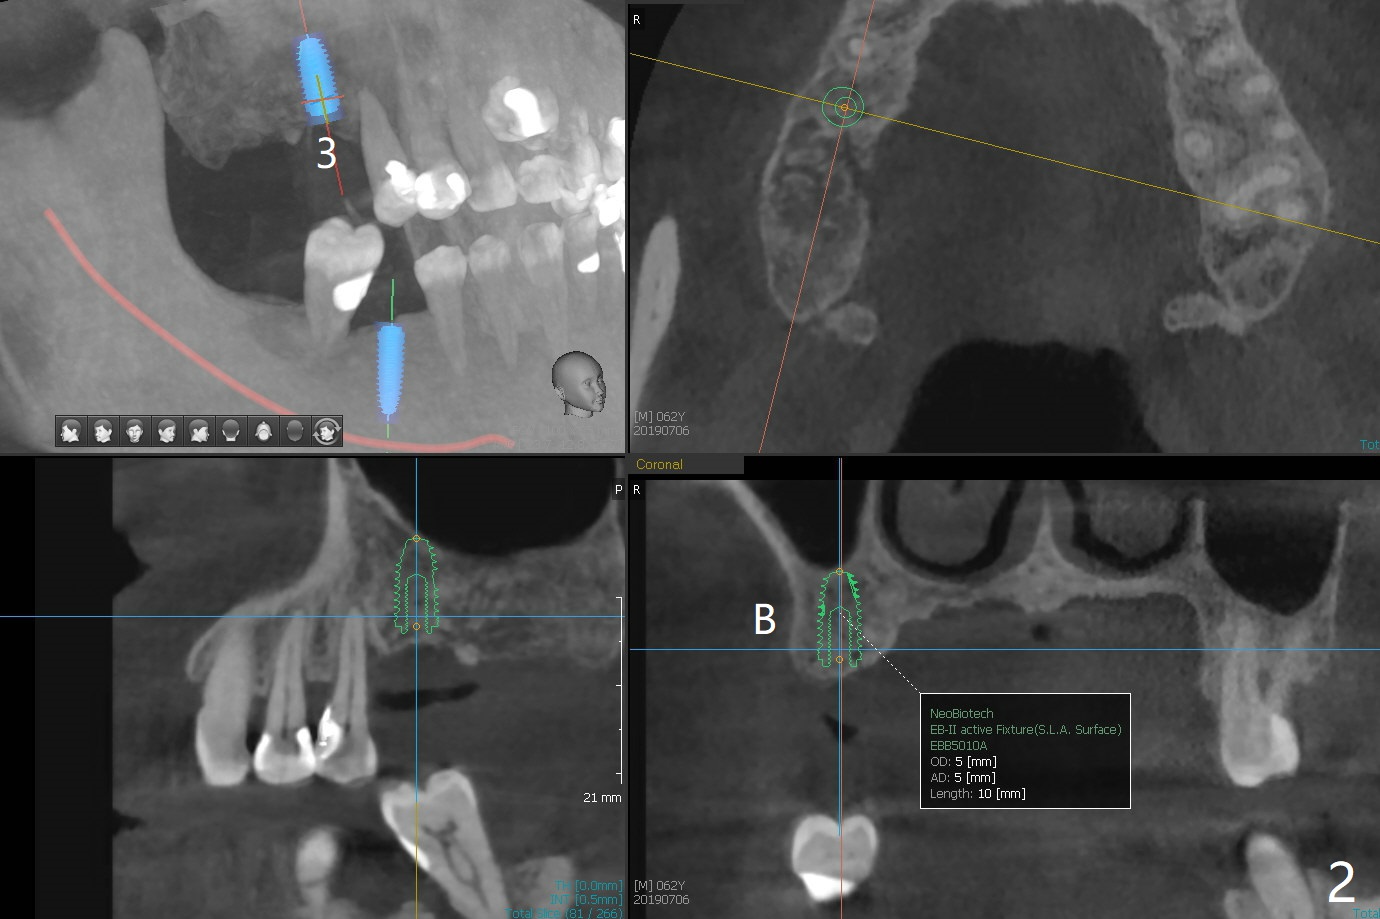

In spite of financial constraint of a 62-year-old man with a dental insurance with limited annual allowance, CT and impression are taken for surgical guides for #3 and 30 at the same time in order to establish a better occlusion over the posterior overjet (Fig.1). The implant at #3 will be placed this calendar year (Fig.2), while the one at #30 early next year (Fig.3). The tooth #31 will be extracted with #30 implant placement. The bone harvested from osteotomy will be mixed with Osteogen and placed in the #31 socket. An immediate provisional at #30 will be extended distal to cover #31 socket. Use Osteogen or Collagen plug if necessary.